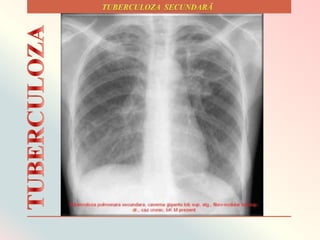

Tipuri de infiltrate tuberculoase secundare.

Infiltrat tuberculos subclavicular dreapta

Cavernǎ TBC cu

pereți subțiri,

intens opaci,

subclavicular

dreapta (cavernǎ

fibroasǎ)

Reprezintǎ o etapǎ mai avansatǎ, cȃnd TBC infiltrativǎ a ajuns ȋn faza de

cazeificare și lichefiere devenind forma obișnuitǎ (comunǎ) a tuberculozei

adultului.

Tuberculoza fibro-cazeoasǎ cavitarǎ